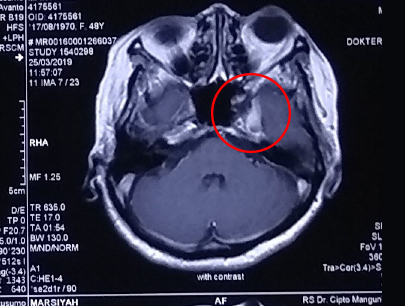

(Wanita, 48 tahun)

Diagnosis: Tumor Sphenoid Wing 1/3 Medial Curiga Meningioma

Sebelum Gamma Knife

• Nyeri Kepala

• Buta mata kiri (tidak bisa melihat cahaya)

• Penonjolan mata kiri

3 bulan Setelah Gamma Knife

• Kebutaan menetap

• Penonjolan mata kiri berkurang

Volume Tumor: 3.45 cm3

Volume Tumor: 2.3 cm3